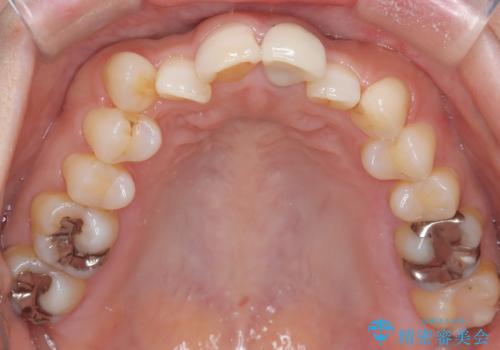

- 「八重歯をきれいにしたい」とのご希望で来院されました。診察の結果、上顎犬歯の萌出スペースが不足しており、典型的な八重歯(叢生)の状態でした。上下の歯の中心(正中)のずれや、奥歯のかみ合わせ(臼歯関係)のアンバランスも見られたため、単に見た目を整えるだけでなく、全体的な機能改善も必要と診断しました。

スペースを確保するために抜歯を行う選択肢もありましたが、歯列の幅や骨格とのバランスから判断し、上顎の奥歯を後方に移動させることでスペースを作る方針を立てました。そのため、まずリンガルアーチ(内側に装着する固定式装置)を用いて奥歯を遠心移動させ、その後ワイヤー矯正で歯列全体を整える治療計画を立案しました。

初期段階では、リンガルアーチを上顎に装着し、奥歯を少しずつ後方へ移動させていきました。これにより前歯部の歯列に十分なスペースを確保。その後、マルチブラケット(ワイヤー矯正)を用いて、突出した八重歯を正しい位置に誘導しながら、歯並び全体を整えていきました。